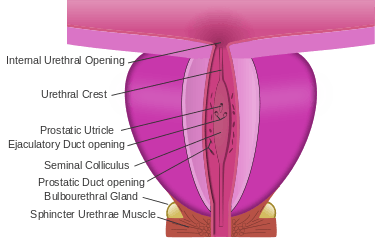

The secretory epithelium is mainly pseudostratified, comprising tall columnar cells and basal cells which are supported by a fibroelastic stroma containing randomly oriented smooth muscle bundles that's continuous with the bladder. The epithelium is highly variable and areas of low cuboidal or squamous epithelium are also present, with transitional epithelium in the distal regions of the longer ducts.[8] Within the prostate, the urethra coming from the bladder is called the prostatic urethra and merges with the two ejaculatory ducts.[9]

During male ejaculation, sperm is transmitted from the vas deferens into the male urethra via the ejaculatory ducts, which lie within the prostate gland. It is possible for some men to achieve orgasm solely through stimulation of the prostate gland, such as prostate massage or receptive anal intercourse.[18][19][20]

Vertical section of bladder, penis, and urethra. Dissection of prostate showing prostatic urethra.

Dissection of prostate showing prostatic urethra.